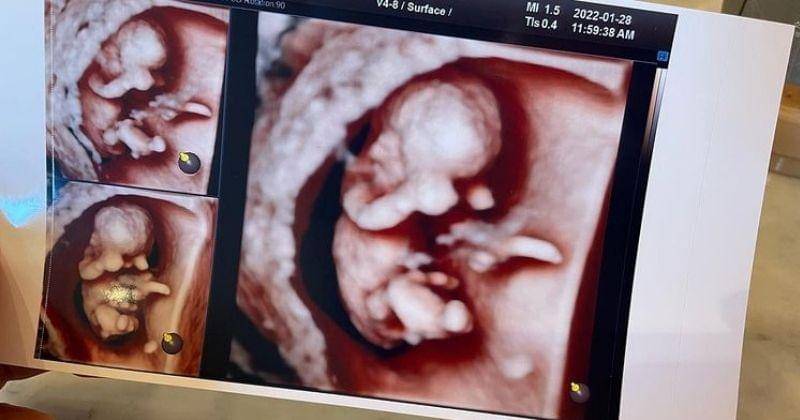

1. Jason membagikan sonogram di Instagram dan menulis pesan haru

Di hari yang sama, Jason mengunggah sonogram anak pertama mereka. Secara khusus, Jason mengungkapkan isi hatinya melalui tulisan singkat.

"Senang bertemu denganmu, aku seorang ayah sekarang," tulisnya pada unggahan itu.